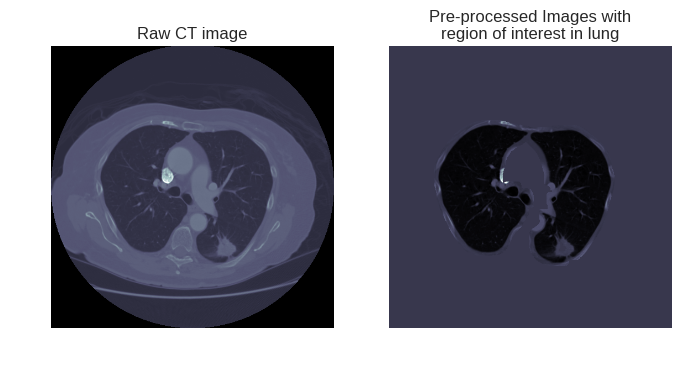

最后再看一下提取的效果如何:

右图将进一步的放入深度学习模型,进行肺部结节的进一步检测。